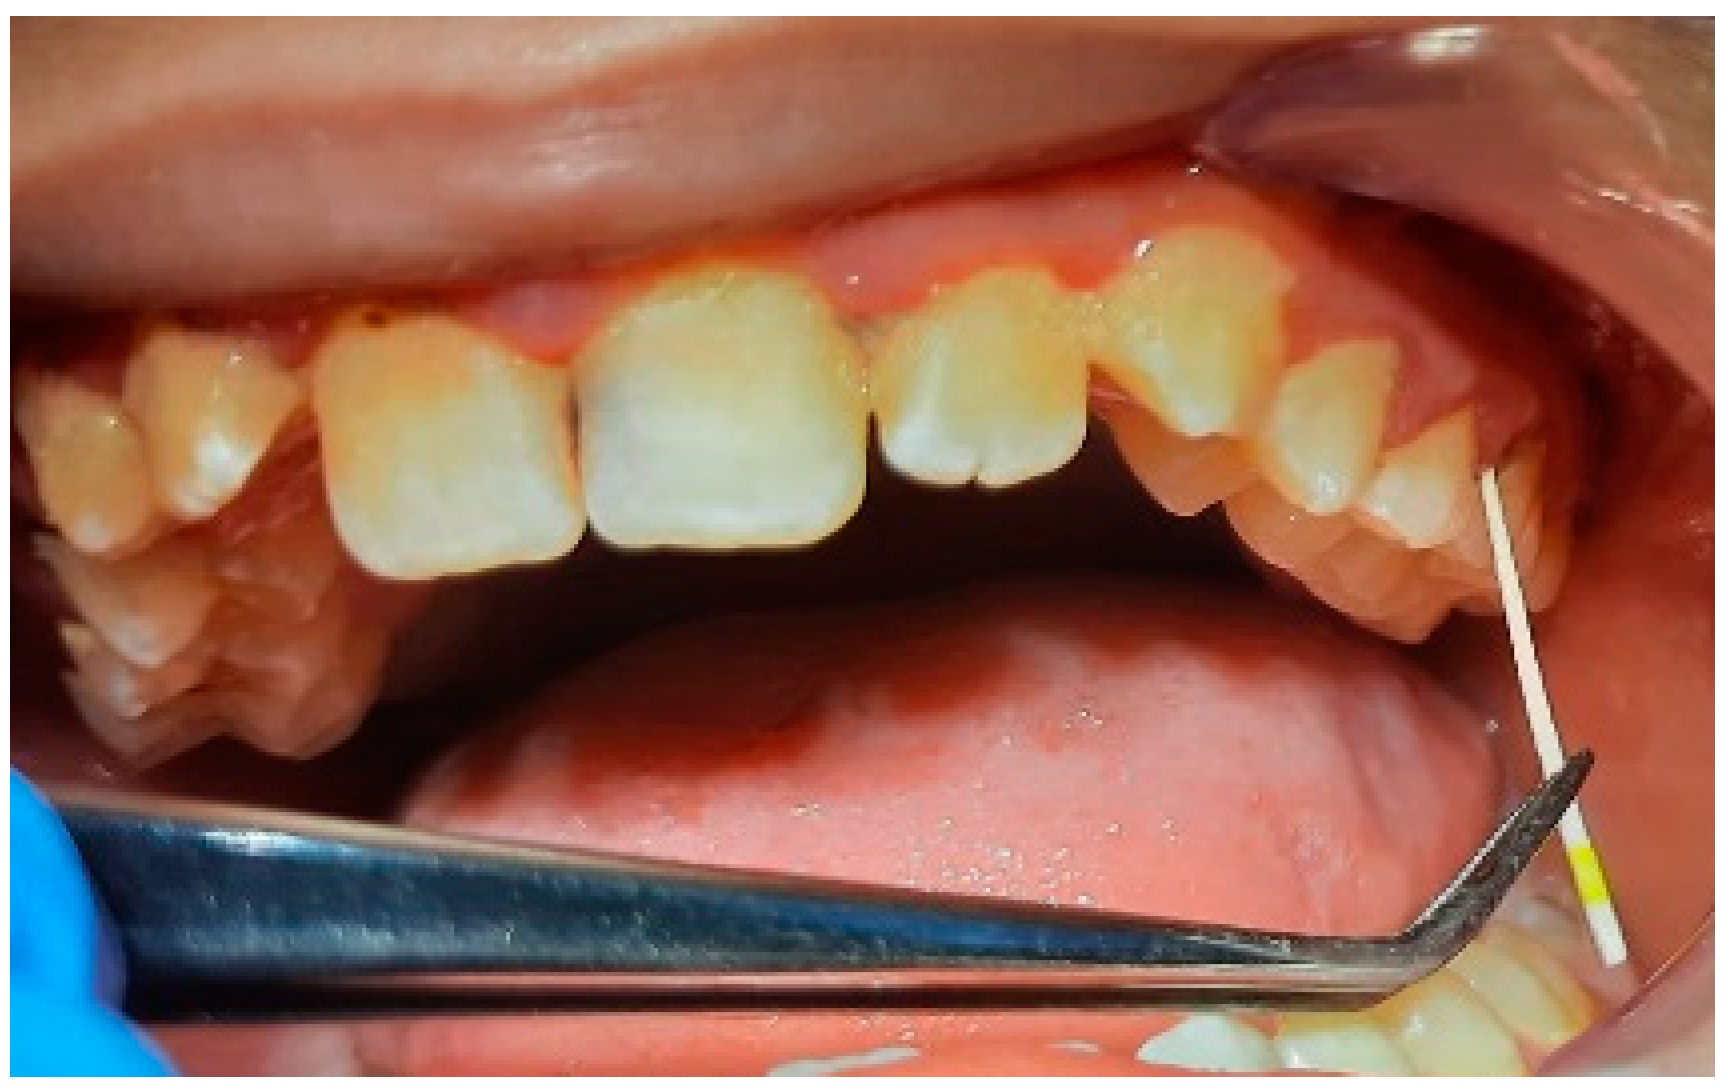

2.2. Clinical Examinations

2.5. Specialist Treatment